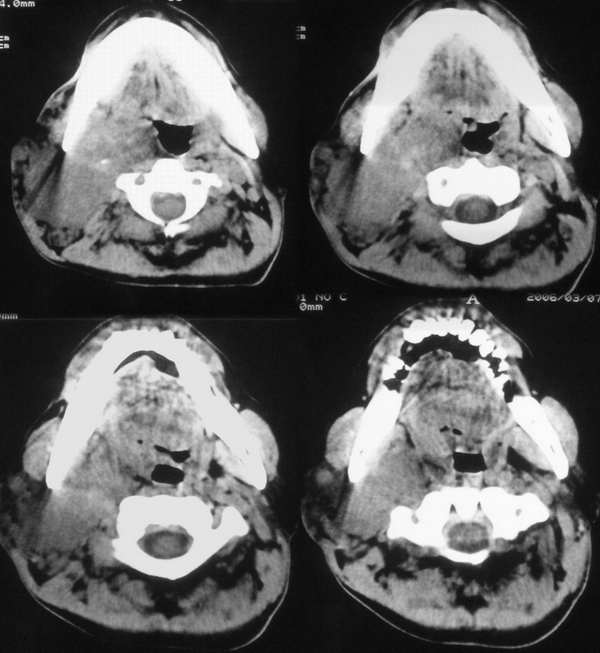

以下是引用wawaquan在2006-3-12 20:00:00的发言:[br]右颈部低密度包块,范围较大,内侧达咽侧壁,外侧达皮下,包绕颈部大血管;增强后明显不均匀强化。[br]男,42岁,颈部无痛性包块20年余,渐进性增大,近期疼痛。[br]考虑:淋巴血管瘤可能大。

以下是引用usa911go在2006-3-12 20:02:00的发言:[br]右侧颈部占位性病变,强化明显,血管有包饶,无钙化,其内有坏死灶。考虑淋巴瘤